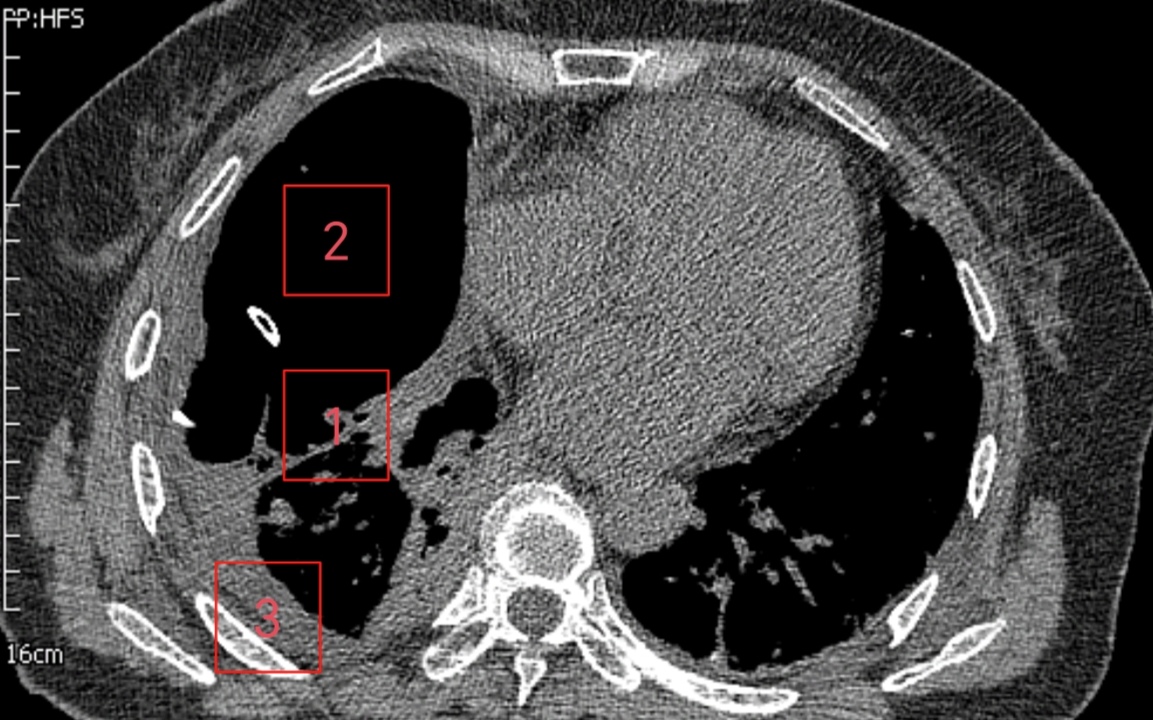

患者是一位61岁女性,诊断右侧巨型肺大疱已2年,近1周突发不明原因高热伴胸痛,体温最高达39.0℃。就诊于清华大学附属垂杨柳医院急诊科。经胸部CT检查,提示右侧巨型肺大疱(最大直径约15cm)内出现液平(最大直径约10cm),考虑疱内感染。虽经规范内科抗感染治疗,高热、胸痛症状未显著缓解,且进行性加重至无法脱离氧气支持,遂紧急转入我科进一步诊治。在胸外科主任崔健指导下,胸外科医师赵洋乐即刻联系超声科,在其精准引导下实施右侧肺大疱内及右侧胸腔脓液闭式引流术,成功引流出超过1000ml坏死液体。术后患者体温迅速恢复正常,胸痛显著缓解,脱氧状态下可自如活动。然病灶尚未根除,鉴于患者既往肺功能低下且近期高热导致营养状况不佳,需先行呼吸功能锻炼与全面营养支持,再择期手术。术前评估时,崔健围绕患者手术潜在风险,表示:1.胸腔内广泛粘连可能导致腔镜操作困难,需中转开胸;2.术中大面积渗血引发血压剧烈波动;3.肺大疱基底范围过大致无法彻底根治性切除;4.术中感染控制不佳可能引发术后严重胸腔感染及伤口不愈;5.肺功能低下致术后脱机困难。

▲闭式引流前

▲闭式引流后